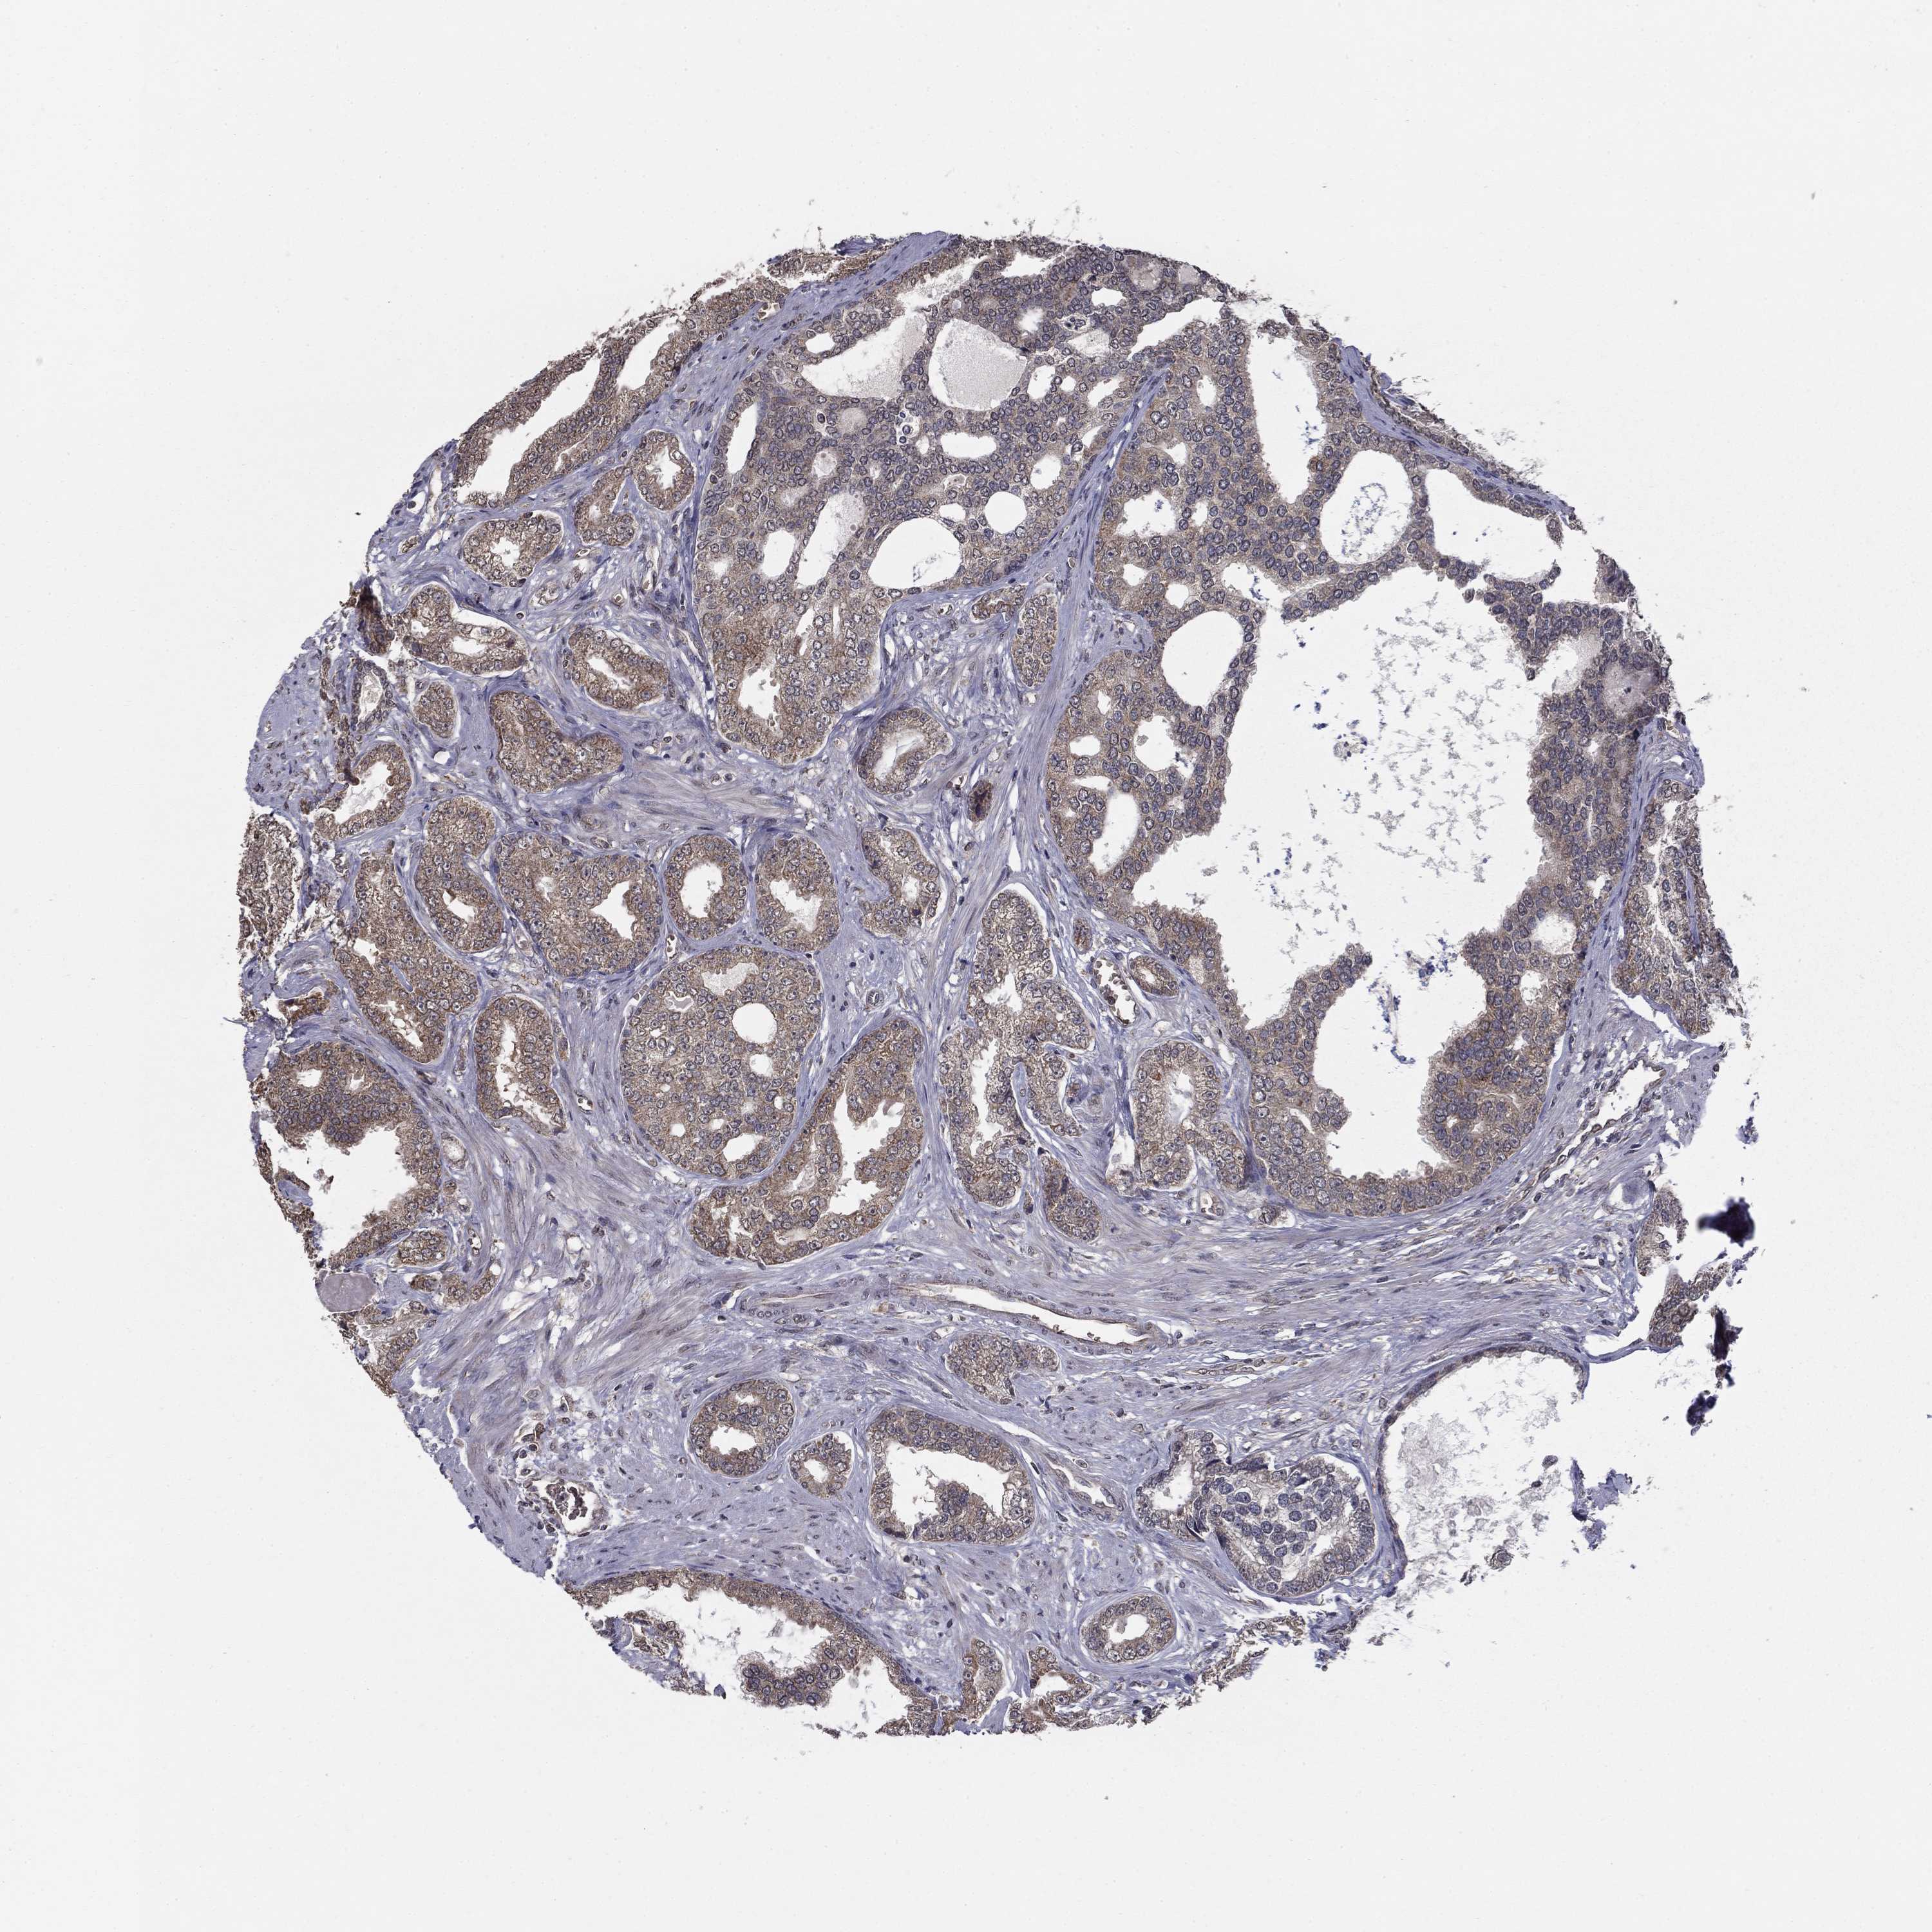

PROSTATE CANCER - Protein expressioni

A mouse-over function shows sample information and annotation data. Click on an image to view it in a full screen mode. Samples can be filtered based on level of antibody staining by selecting one or several of the following categories: high, medium, low and not detected. The assay and annotation is described here.

Note that samples used for immunohistochemistry by the Human Protein Atlas do not correspond to samples in the TCGA dataset.

Antibody stainingi

Antibody staining in the annotated cell types in the current human tissue is reported as not detected, low, medium, or high, based on conventional immunohistochemistry profiling in selected tissues. This score is based on the combination of the staining intensity and fraction of stained cells.

Each image is clickable and will lead to virtual microscopy that enables deeper exploration of all samples and also displays staining intensity scores, fraction scores and subcellular localization as well as patient and tissue information for each sample.

Antibody HPA006584

Antibody HPA061679

Staining

High

Medium

Low

Not detected

Intensity

Strong

Moderate

Weak

Negative

Quantity

>75%

75%-25%

<25%

None

Location

Nuclear

Cytoplasmic/membranous

Cytoplasmic/membranous,nuclear

Adenocarcinoma, Low grade

Adenocarcinoma, High grade

Adenocarcinoma, NOS